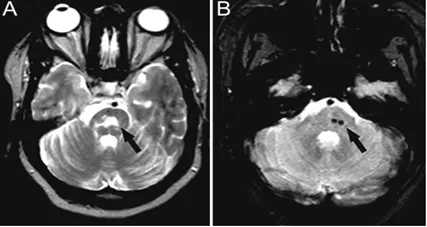

彈性假黃瘤(PXE)是一種遺傳性疾病,以進行性鈣化和彈性纖維變性為特徵,主要影響面板、眼睛、胃腸道和心血管系統。腦MRI特徵包括腔隙性梗死、WMH和CMBs(圖7)。

圖7 43歲女性PXE患者,T2WI高訊號提示腦橋梗死(A);T2WI低訊號提示微出血(B)